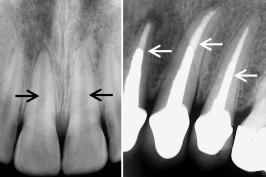

A raiz sumiu: dentes são reabsorvidos

15.03.2025 07h18

COLUNISTA

O que significa um dente anquilosado?

15.02.2025 06h07